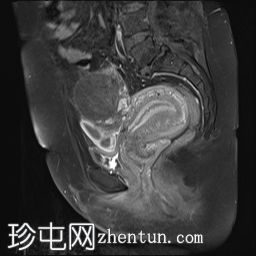

冠状位

T1加权像

可见子宫外腹腔内妊娠囊,内含胎儿组织。

该妊娠囊向后推移子宫,并与剖宫产瘢痕凹陷处紧密相连。

该妊娠囊与相关肠袢无法分离。可见其与性腺血管密不可分,且性腺血管明显突出。

胎盘位于妊娠囊后方,紧贴子宫前壁。

沿妊娠囊下缘可见一处异质性局灶性积液,最大轴向尺寸约为 8.4 × 5.5 cm,T1 加权像呈异质性高信号,T2 加权像呈异质性中等信号,T1 脂肪抑制序列未见信号下降,提示为血液成分。该积液压迫膀胱。

可见周围脂肪间隙呈条索状改变。

左侧卵巢无法辨认。

右侧卵巢未见实性或囊性肿块。

子宫体积增大,后倾,子宫内膜厚度约 1 cm,子宫下段前壁可见局灶性变薄(既往子宫瘢痕)。子宫连接区完整,未见肌层肿块。可见子宫内膜腔边缘有血性分泌物。